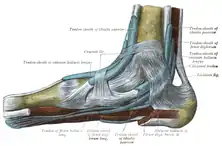

The mucous sheaths of the tendons around the ankle. Medial aspect. (Tendon of flexor hallucis longus labeled at bottom left.) | |

This tendon lies in a groove which crosses the posterior surface of the lower end of the tibia, between the medial and lateral tubercles of the posterior surface of the talus, and the under surface of the sustentaculum tali of the calcaneus; in the sole of the foot it runs forward between the two heads of the flexor hallucis brevis, and is inserted into the base of the last phalanx of the great toe. The grooves on the talus and calcaneus, which contain the tendon of the muscle, are converted by tendinous fibers into distinct canals, lined by a mucous sheath.